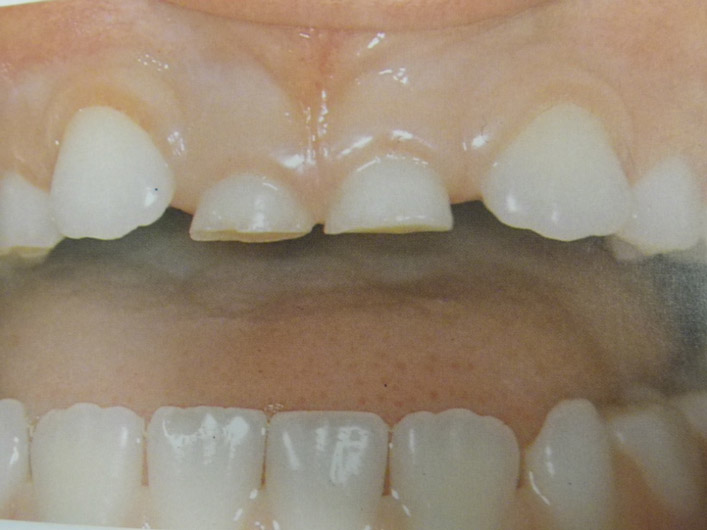

Τερηδόνα βρεφικής και νηπιακής ηλικίας ή τερηδόνα θηλασμού

Η τερηδόνα βρεφικής και νηπιακής ηλικίας εμφανίζεται σε μικρά παιδιά ηλικίας 2 έως 5 ετών, τα οποία έχουν τερηδονισμένα ένα ή και περισσότερα νεογιλά δόντια. Η τερηδόνα αυτής της μορφής οφείλεται σε λάθος τρόπο διατροφής του παιδιού και μπορεί να εξελιχθεί γρήγορα και σε μεγάλη έκταση επηρεάζοντας το σύνολο το δοντιών που βρίσκονται στο στόμα.

Η κυριότερη αιτία εμφάνισης της τερηδόνας αυτής της μορφής είναι το τάισμα με το μπιμπερό ενώ το παιδί κοιμάται. Κατά τη διάρκεια του ύπνου η ποσότητα του σάλιου μειώνεται και το γάλα, ανεξάρτητα αν περιέχει ή όχι ζάχαρη, παραμένει πάνω στα δόντια και προκαλεί τερηδόνα. Ακόμη και το μητρικό γάλα μπορεί να έχει τις ίδιες συνέπειες, εφόσον το παιδί θηλάζει κατά βούληση κατά τη διάρκεια της νύχτας.